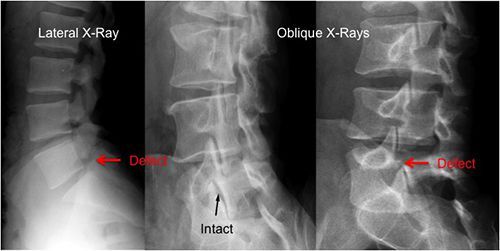

+ Hình ảnh tổn thương cột sống: ở giai đoạn muộn, Xquang thường quy có thể thấy hình ảnh xơ hóa các dây chằng bên hoặc dây chằng trước cột sống, biểu hiện bởi các cầu xương, khiến cột sống có hình cây tre. Có thể thấy hiện tượng xơ hóa các dây chằng liên gai (hình ảnh đường ray xe lửa), có thể calci hoá đĩa đệm, tổn thương khớp liên mấu sau, tổn thương khớp xương sườn đốt sống. Ngoài ra, có thể thấy hình ảnh loãng xương: hình ảnh tăng thấu quang, đốt sống cong lõm hai mặt. Đôi khi (hiếm gặp) có hình ảnh gãy cầu xương đốt sống hoặc gãy cung sau.

( hình ảnh đốt sống tổn thương do viêm cột sống dính khớp )